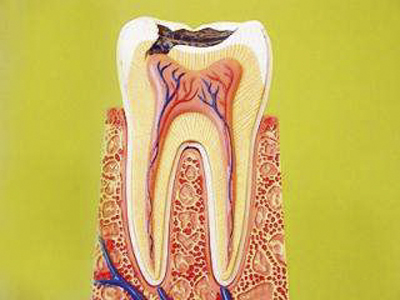

牙髓炎圖片

A:發生牙髓炎以後,如果不進行及時治療,發炎的牙髓會逐漸範圍擴大,導致更多的牙神經發炎甚至壞死,最後導致牙髓腔內的牙髓組織全部壞死,壞死物質無法從冠方的牙髓腔導出,只能向根尖部移動和滲出,會導致局部發生根尖周炎。牙髓炎如果不處理會導致局部炎症的……